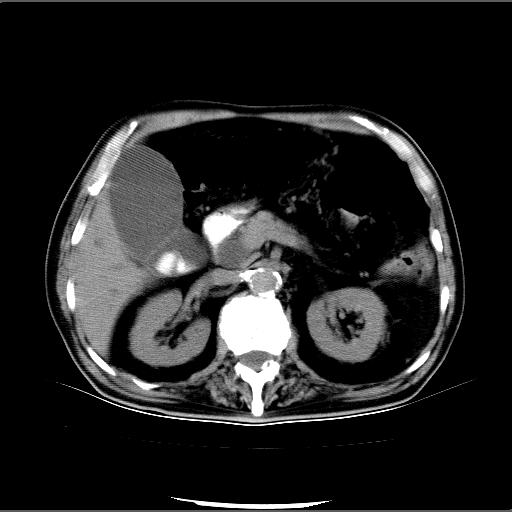

患者男82岁,黄染,发热10天,无腹痛。

1胆总管下端结石伴肝内外胆管扩张;2胆囊颈部结石伴胆囊积液

胆囊多发结石,胆囊积液;胆总管中下段结石,中上段扩张。

胆总管下段结石伴胆道系统扩张;胆囊炎伴胆囊结石.

有时胆总管下段结石的密度并不是均匀的高密度,而是以高密度为主的伴中心等密度的混合物,这与胆道结石的多样性有关,少数时候诊断困难时应结合临床病史,症状等,还有增强扫描都可以帮助明确诊断!!常与胆道蛔虫伴钙化鉴别!

1、胆总管壶腹部结石并胆总管、胆囊及肝内胆管扩张。2、胆囊多发结石。3、两下胸膜局限性增厚。4、胃体部大弯侧胃壁稍厚,建议:多量饮水后增强ct扫描除外占位性病变。

十二指肠乳头旁憩室伴胆总管下段结石,胆囊结石

此病例有结果了:患者术后为:胆总管下段结石伴胆道系统扩张;胆囊炎伴胆囊结石。

各位战友分析的都很正确,是一个典型的病例。